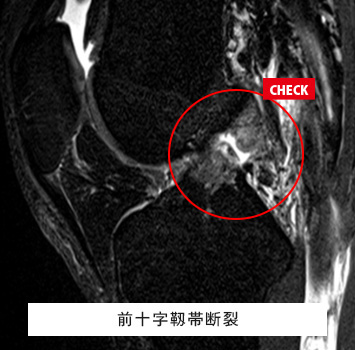

膝(ひざ)MRIチェック

このような方におすすめします。

• 立ち上がりや歩き始めの痛み、階段の昇降時の痛みがある

• スポーツや仕事で膝関節を痛めた、動かしづらい

• レントゲンでは分からない半月板や靱帯の怪我が心配

筋肉と関節痛みのMRIチェック名古屋なら

レントゲン検査では分からない骨、筋肉、腱、関節唇などの様子が

がたった10分の検査で評価出来ます!

長引く膝痛、レントゲンで異常なし

外傷後膝が曲がらない、レントゲンで異常なし

料金(片側):¥17,600(税込)

ご予約はこちら

半月板損傷、前十字靱帯損傷、後十字靱帯損傷、内側側副靱帯損傷、外側側副靱帯損傷、変形性膝関節症、骨軟骨損傷、離断性骨軟骨炎、滑膜炎、ベーカー嚢腫、骨腫瘍、疲労骨折 など